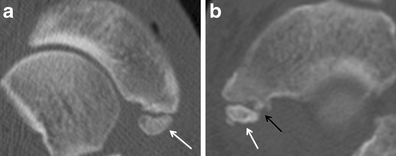

Degeneration at a synchondrosis. a Long-axis axial CT image shows an apparently normal type II accessory navicular (arrow) with a preserved synchondrosis with the navicular tubercle. b In comparison, this long-axis axial CT image of a different foot depicts increased sclerosis and fragmentation of a type II accessory navicular (white arrow) and fragmentation of the navicular tubercle at the synchondrosis (black arrow) consistent with degenerative change